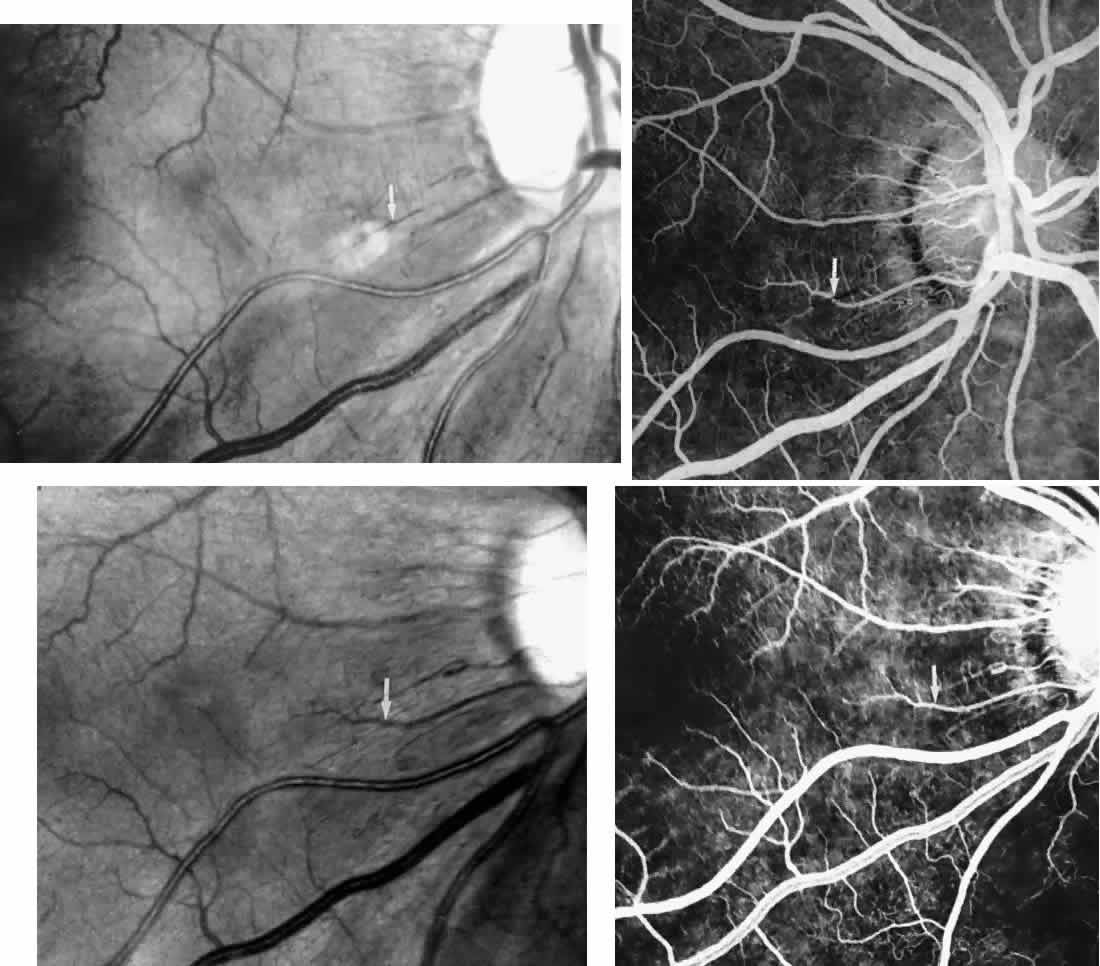

The occluded arterioles may be invisible or may have a “silver-wire” or chalk-white appearance, as first described by Goodman and colleagues39 (Fig. 21). Fluorescein angiography may demonstrate an abrupt complete occlusion at the interface between peripheral nonperfused and posterior perfused retina. Frequently, this occlusion will take place just distal to a branching vessel, giving the appearance of a freshly pruned rose bush. The nonperfused anterior peripheral retina will have a grayish brown appearance and on fluorescein angiography will appear blurred without clearly defined fundus markings.

STAGE II: PERIPHERAL ARTERIOLAR-VENULAR ANASTOMOSES. Following occlusion of the terminal arterioles, anastomotic channels form to channel the blood from the occluded arteriole to the nearest venules. These anastomoses form at the interface between the perfused and nonperfused retina. Most likely, they are dilated preexisting capillaries rather than new vessels, since they do not leak on fluorescein angiography. The redirection of blood flow is probably due to hydrostatic forces (Figs. 22 and 23).

|